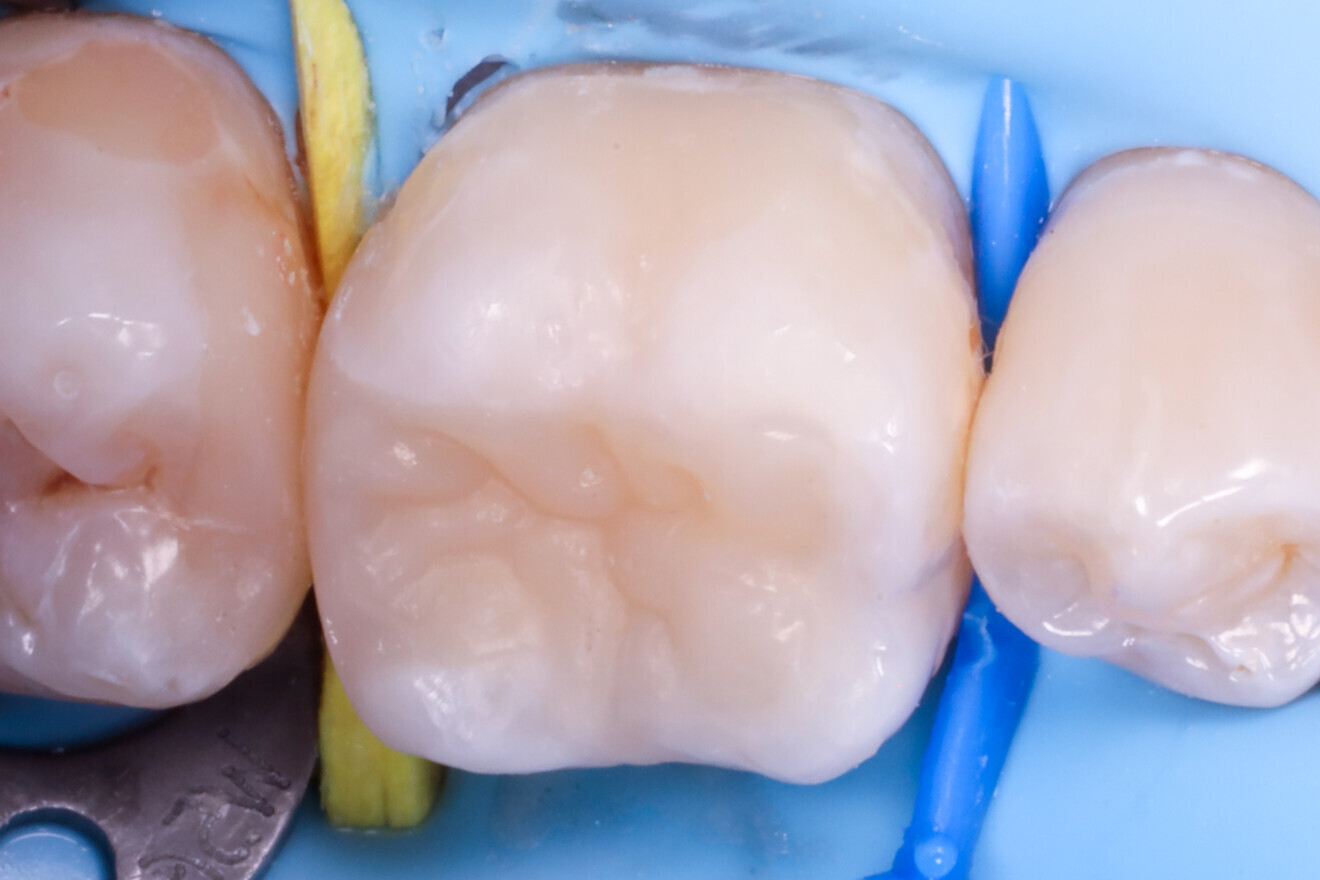

Fig. 1: Pre-op view of the mandibular first molar with existing composite restorations. (All images: Dr Péter Farkas)

Treatment focused on a mandibular first molar with existing Class I and V composite restorations (Fig. 1). The tooth was asymptomatic, and cold testing revealed a normal response. A distal carious lesion, which was not clinically visible, was first suspected during routine screening and its extent clearly identified on the panoramic radiograph (Fig. 2).